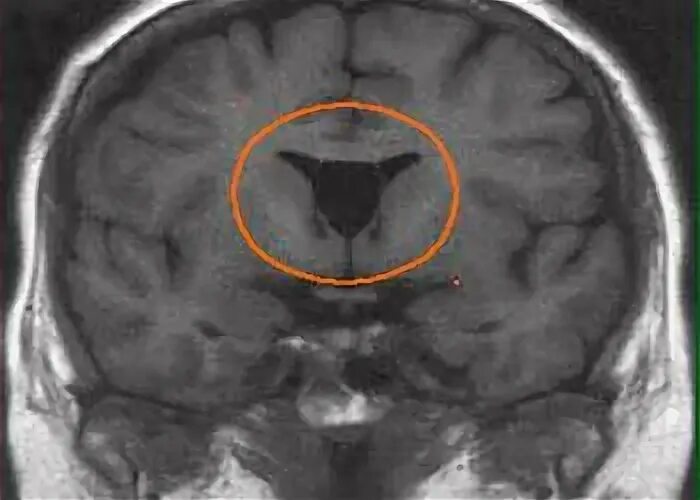

Незаращение листков прозрачной перегородки